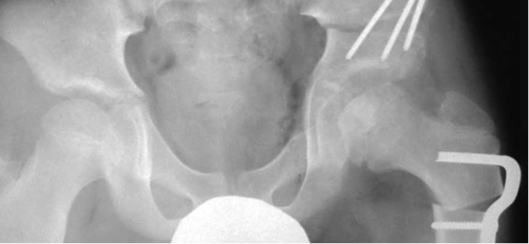

10歳男子の右ペルテス病。この年齢になると骨頭そのものが大きくなってくる。その為、内反骨切りだけで骨頭を臼蓋の中に入れようとすると内反角度が大きくなり、結果的に脚長差が著しくなってしまう。あらかじめ骨盤骨切りを行い、ある程度臼蓋で骨頭を覆っておくと、内反角度を小さく抑えることができる。